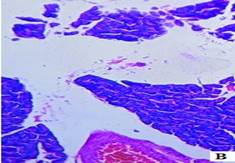

The histopathological studies of the pancreatic tissues are shown in (fig. 3). Normal rats showed the normal architecture of the pancreas with the preserved islet of Langerhans cells (fig. 3A). Induction of diabetes using Streptozotocin resulted in hyalinization of islets of Langerhans cells with focal mild degenerative changes, mild fibrosis, dilated and congested vessels along with focal chronic inflammatory cell infiltrate in diabetic rats (fig. 3B). HFT control rats showed mild edema of islets of Langerhans cells, thick-walled and congested vessels, focal lymphocytic infiltrate exhibiting focal edematous changes (fig. 3C). The abnormal histopathology of the pancreas due to Streptozotocin-induced diabetes was reversed in the Glibenclamide, and EAFBN treated diabetic animals.

The recovery of standard Glibenclamide treated group was evident as near normal architecture with preserved islet cells and mild edema (fig. 3D). The resulted in EAFBN (100 mg/kg, 200 mg/kg & 400 mg/kg) treated groups mild hyalinization islets of langerhans cells with focal mild degenerative changes when compared to untreated diabetic rats. It can be noted that the islets of langerhans cells regenerated in the treatment groups (fig. 3E,3F& 3G).

Fig. 3: Histology of control and treated rat pancreas of antidiabetic studies. A) Control rat, B) Diabetic control, C) HFT control, D) Standard, E) EAFBN (100 mg/kg), F) EAFBN (200 mg/kg) and G) EAFBN (400 mg/kg)